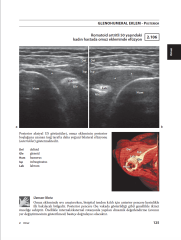

Kas-iskelet ultrasonu kullanıcıya bağlıdır, bu nedenle bir akıl hocalığı ve 'bakım' eğitimiyle güçlü bir şekilde eğitime ihtiyaç duymaktadır. Buna göre, bu kitabın asıl amacı, en sık taranan kas-iskelet patolojileri ile ilgili birçok örnek sunmak ve böylece uzun süreli denetlenen eğitimin boşluğunu doldurmaktır. Kitabın bölümleri, anatomi atlaslarındaki gibi, baş ve boyundan başlayıp ayaklarına kadar olan bölgeler şeklinde düzenlenmiştir. Her bölümde, alt bölümler de anatomik yapılara göre düzenlenmiştir. 500 görüntü bulunmaktadır. Metin esas olarak klinik / fizik muayene bulguları içeren uzun şekil içeriklerine dayanmaktadır. Önemli bir nokta da, kitabı okurken birçok sayfanın altındaki "Uzman Notu" olarak adlandırılan parçaları göreceksiniz. Bu yorumlar elbette kitabın en seçkin tarafıdır.